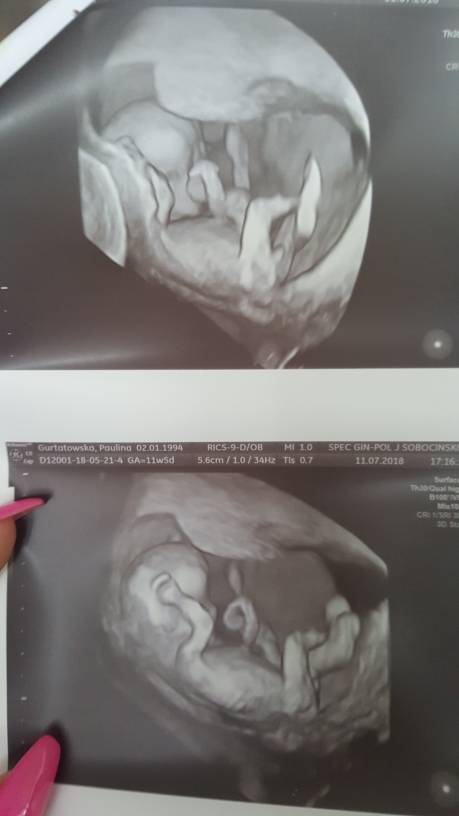

Super! A zdjecie cudne [emoji7] co do butów, pierwsze o jakich pomyślałam to wlasnie niebieskie chabrowe [emoji173]I ja po wizyciewszystko w jak najlepszym porzadku, wszystkie parametry w normie. 6,5cm długości. Mój był zaskoczony, że to juz tak wszystko ukształtowane i ręce i nóżki i w ogóle mini czlowieczek taki

jak wrocimy do domu, to wrzucę wam zdjęcie. Aha, no i prawdopodobnie chłopak

Gratuluje [emoji4] a plec jaka?Zobacz załącznik 878890 odebrałam wyniki NIFTY, z USG wszystko Ok. Dziecko rozwija się prawidłowo i wygada na zdroweteraz czekam na połówkowe.

Piekne [emoji7]Jak tak wstawiacie swoje maleństwa to też wstawię [emoji4]podobno chłopak [emoji16] siusiaka widać hehe xDZobacz załącznik 878917